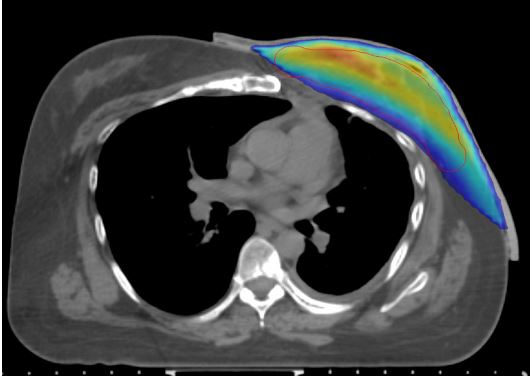

ABC Medical Center - Post-Mastectomy Left Breast EBRT Using 3D Printed Bolus - Case Study

This case provides an example of how Adaptiiv’s software can be used to generate a customized uniform thickness bolus for an irregular surface region. 3D printed bolus enhances clinical precision, improves operational efficiency, and provides greater access to personalized care.